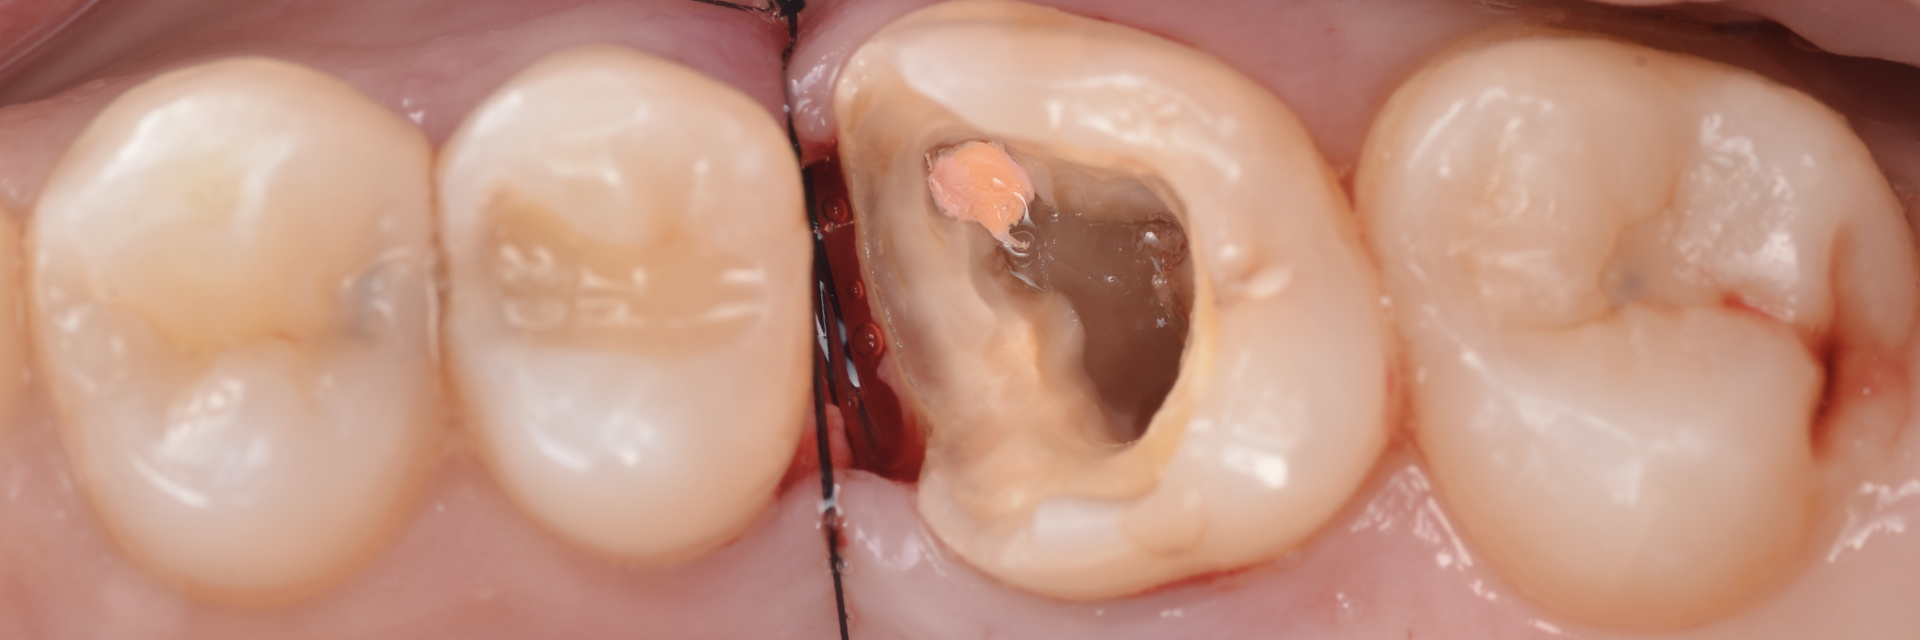

治療内容 まず、歯肉の深い部分まで虫歯が進行し、根っこの先に膿が溜まっていた為、歯肉を外科的に下げ、根管治療をしました

後ほど小臼歯部と第二大臼歯にはダレクトボンディング、第一大臼歯にはセラミック治療を行いました